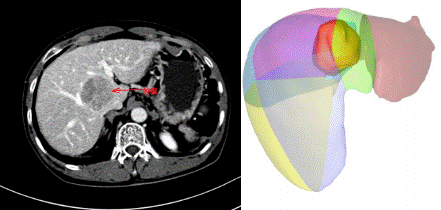

勇闖“禁區(qū)”!——瀘州市中醫(yī)院再攀技術(shù)高峰,成功開展“剝蛋黃”手術(shù)經(jīng)肝臟正中裂將肝臟劈開,在布滿粗大血管的肝臟背側(cè),將腫瘤從被血管包繞的肝臟尾狀葉切除,并最大限度保留正常肝組織。該手術(shù)猶如“火中取栗”,要求手術(shù)醫(yī)生必須有“庖丁解?!卑愕木珳?,因此,該手術(shù)方式被東方肝膽醫(yī)院的周偉平...